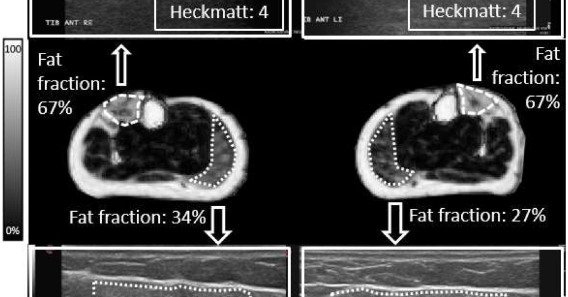

🇪🇺👉Machine learning-driven Heckmatt grading in #FSHD: A novel pathway for musculoskeletal ultrasound analysis 💡Automatic pipeline for muscle ultrasound analysis, leveraging learning and quantitative Heckmatt grading 📰 https://t.co/mVuxqaNhaB